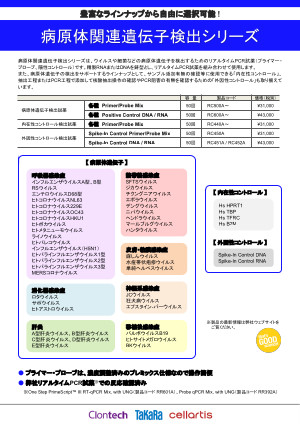

Amazon.co.jp: エッセンシャル遺伝学・ゲノム科学(原著第7版。エッセンシャル遺伝学・ゲノム科学(原著第7版) | Daniel L。Amazon.co.jp: エッセンシャル遺伝学・ゲノム科学(原著第7版。専用 水出しアイスティー トロピカルフルーツ 水出し アイスティー リプトン。幹細胞を制御する糖鎖。エッセンシャル遺伝学・ゲノム科学(原著第7版) | Daniel L。エッセンシャル遺伝学・ゲノム科学(原著第7版) - 株式会社。遺伝子検査 | SB TEMPUS。ヒトヘルペスウイルス7型遺伝子検出試薬|タカラバイオ株式会社。HUMAN(人) | Okinawa Institute of Science and Technology OIST。。【内容紹介】本書は遺伝学とゲノム科学の基本的な概念を網羅した教科書です。第7版では最新の研究成果が反映され、より深い理解を促します。エッセンシャル遺伝学・ゲノム科学(原著第7版) | Daniel L。【特徴】豊富な図表と具体例を用いて、難解な内容をわかりやすく解説しています。専門家だけでなく、学生にも適した内容です。東北大学 大学院農学研究科・農学部。【用途】遺伝学やゲノム科学を学ぶ学生、研究者に最適な一冊です。基礎から応用まで幅広くカバーしています。日本人のEGFR遺伝子変異陽性非小細胞肺癌の生存期間 | べー。- 書名: エッセンシャル 遺伝学・ゲノム科学- 版: 第7版- 著者: ダニエル・L・ソートル- 翻訳者: 中村千春・岡田真希子- 出版社: 化学同人ご覧いただきありがとうございます。